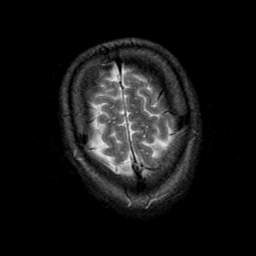

Subacute Stroke, overlay -- Slice #23

[Home][Help][Clinical] Slice 23